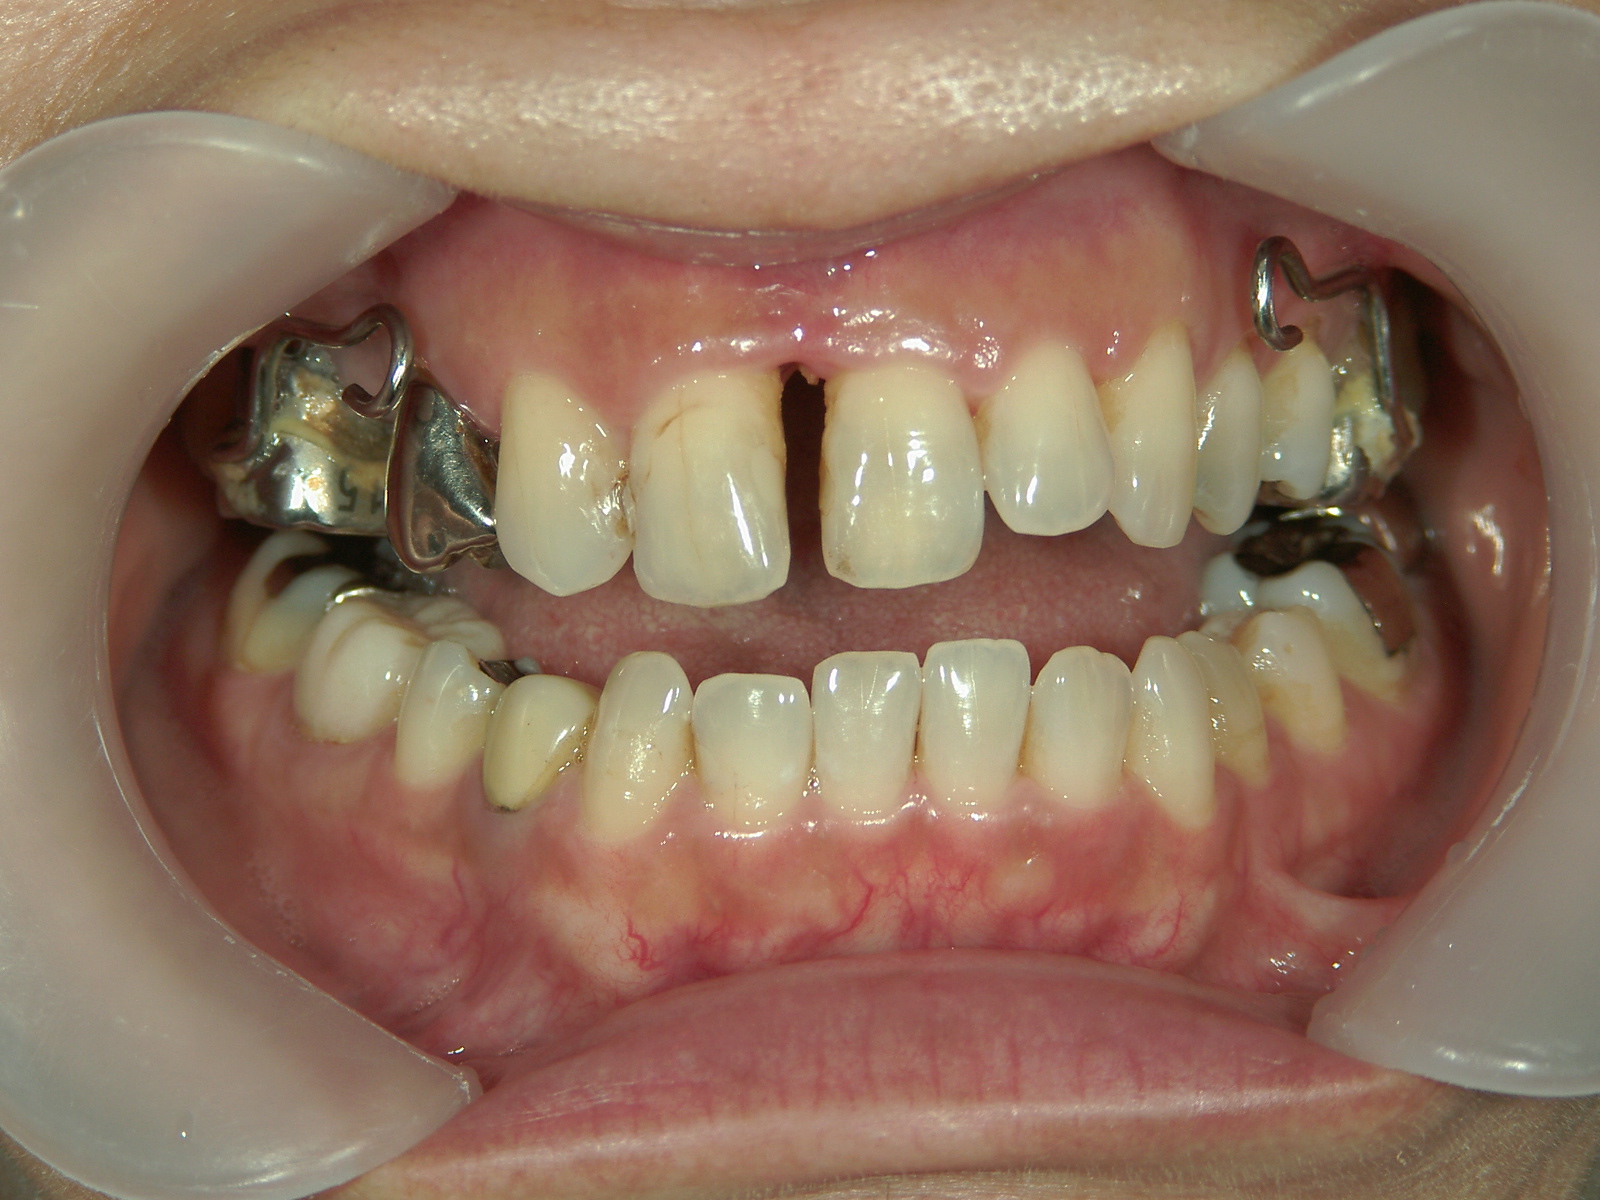

主訴: 受け口、歯並びが気になる。

①患者様はインビザライン矯正をご希望でしたが、上顎骨が小さく、受け口になっているので、インビザライン矯正で治療するために「骨切断OPE」「矯正装置(MSE+フェイスマスク)」で上顎骨を拡大しました。

②右上前歯が内側に入っているため、歯列に入る隙間を作るためにワイヤー矯正を併用し、右上前歯を出しました。